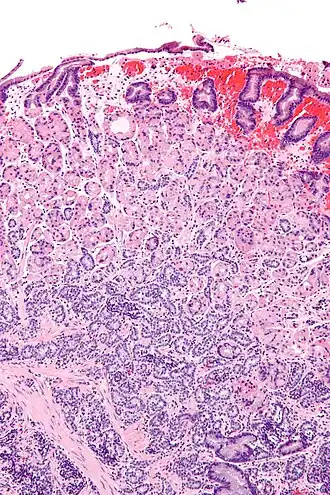

| Micrografia de um tumor neuroendócrino no estômago; coloração H&E. | |

Um gastrinoma é um tumor do pâncreas (aproximadamente em 1/3 dos casos) ou extrapancreático (principalmente na parede duodenal) que segrega gastrina em excesso, o que provoca ulceração no duodeno, estômago e intestino delgado.[1]